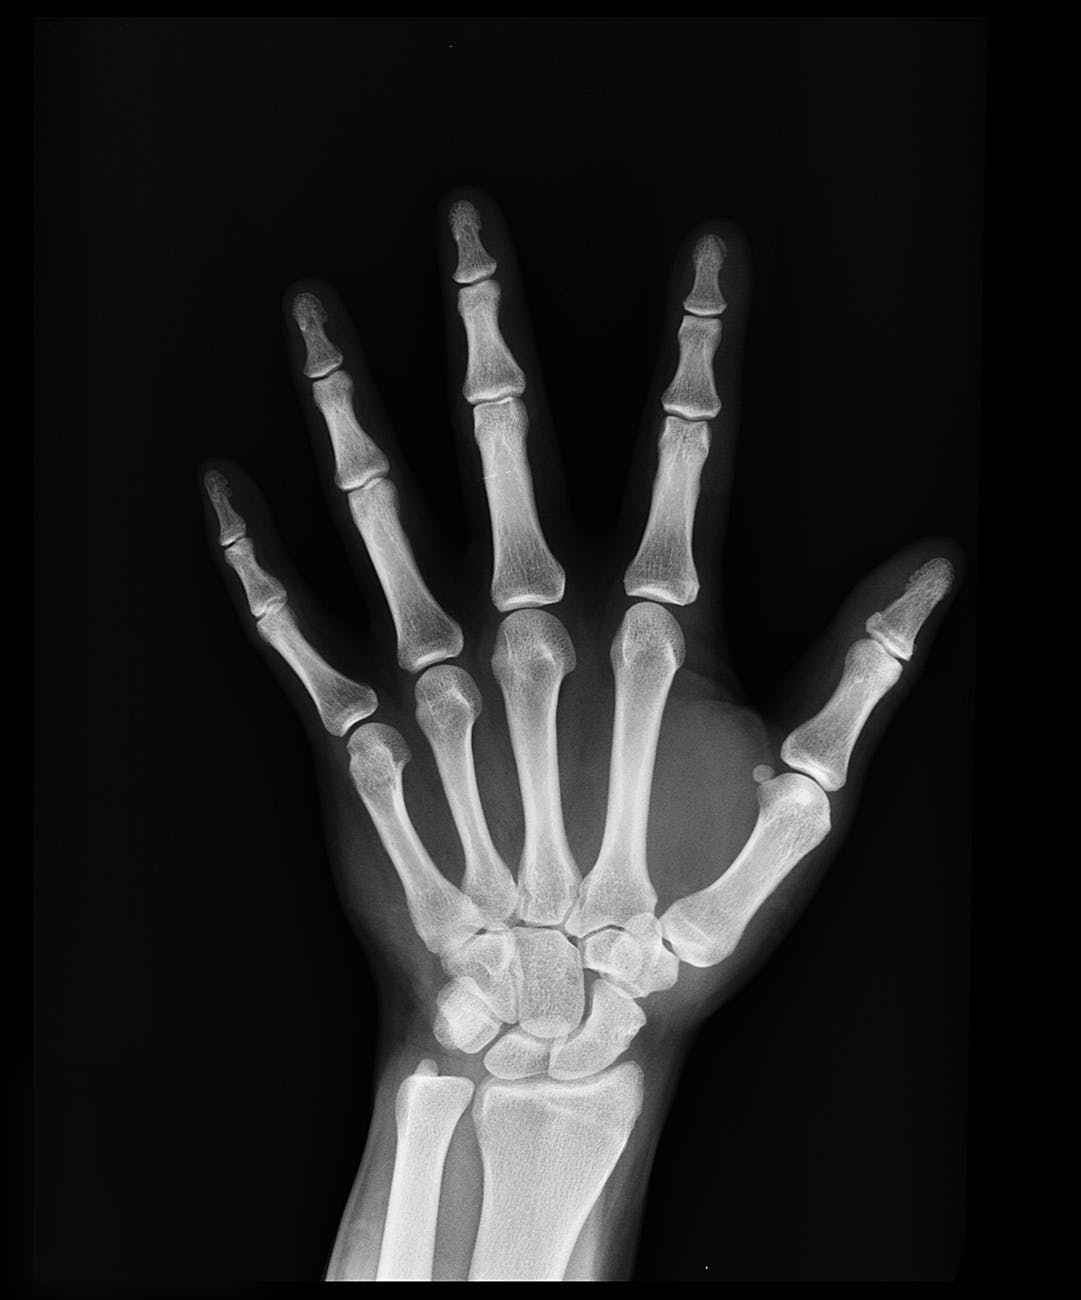

Dentro del tu cuerpo, debajo de los musculos, podemos encontrar unos organismos duros llamados: HUESOS

Ellos tienen varias funciones como la de sostener y dar forma al cuerpo, proteger órganos internos como el cerebro, el corazón y los pulmones; y en conjunto con los músculos permiten el movimiento del cuerpo.

De acuerdo con su forma pueden ser:

Largos: Como los que forman las piernas.

Cortos: Como los que forman las manos.

Planos: Como los que forman el hombro.

Los huesos están unidos por las articulaciones y el conjunto de huesos que forma el cuerpo se llama Esqueleto.